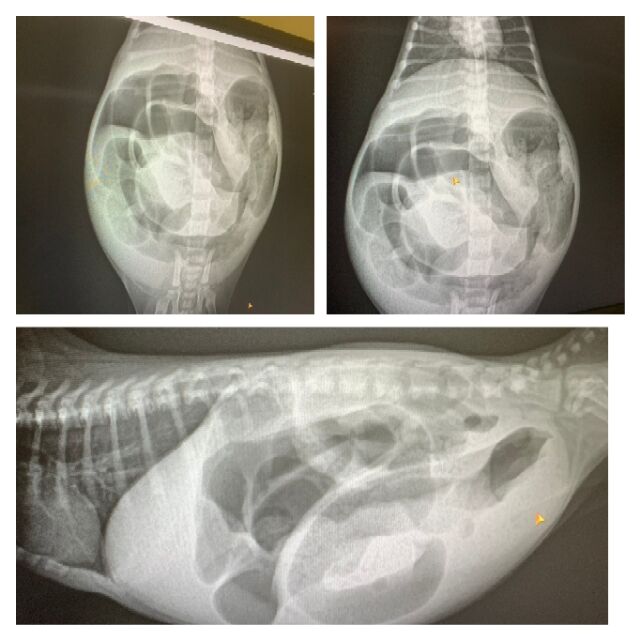

離乳期になっても排便がうまくできず、体重も兄妹の約半分で未熟でした。

何度か通院し、詳しい検査で自力で排便できないことがわかりました。

タイプ4鎖肛です。

300g台のこねこくん…難しい状況とは覚悟の上で…

望みをかけ、人工肛門での処置に踏みきりました。

手術後、こねこくんは懸命に生きてくれています。